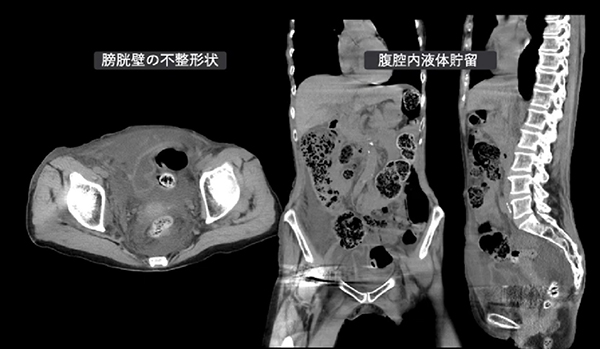

第23回イムスCT研究会はホームページ上で開催し、115名の診療放射線技師が参加しました。

また、『今日から使える!CT撮影テクニック』として春日部中央総合病院 逆井隼技師が「メタルアーチファクトの距離的軽減」、明理会東京大和病院 近藤夏凜技師が「STONE

VOLUME」、『IMSグループ CT症例ネットワーク』として横浜新都市脳神経外科病院 水浦怜主任が「膀胱破裂」について講演していただきました。

アンケートでは、各講演内容とも高評価を得ることができました。今後も実践的で有意義な情報を発信し続けていきたいです。